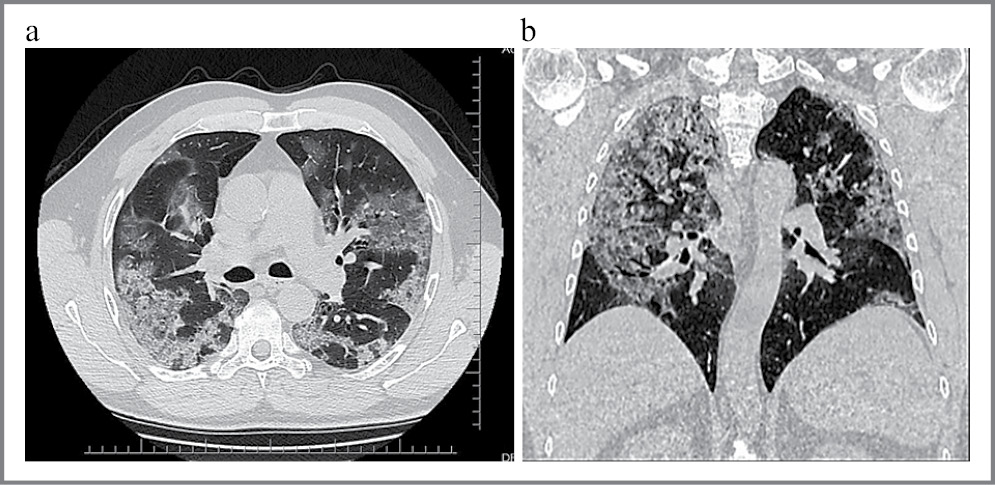

На сегодняшний день «золотым стандартом» диагностики COVID-19 является полимеразная цепная реакция (ПЦР) на выявление РНК вируса с обратной транскрипцией в реальном времени. Данные компьютерной томографии (КТ) у пациентов с первичными ложноотрицательными результатами ПЦР при подозрении на COVID-19 являются существенным дополнением к дифференциальной диагностике (рис. 1) [11, 12].

Рис. 1: а – аксиальная проекция; b – фронтальная проекция. КТ легких у пациента с вирусной пневмонией, вызванной COVID-19. Симптом «матового стекла» и «булыжной мостовой».